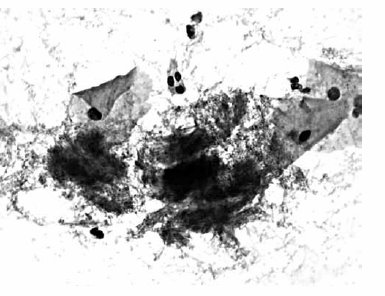

Nas questões de números 46 a 60, assinale a alternativa que melhor corresponde ao diagnóstico do quadro microscópico apresentado.